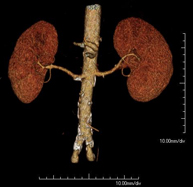

- Renal artery CT angiography

A non-invasive diagnostic test that involves studying the renal arteries by obtaining high-definition anatomical images using CT (computed tomography) equipment and iodinated contrast. With the aid of workstations specialised for arterial studies, the image quality supports 2D and 3D reconstructions. This test is recommended, for example, in patients suffering from refractory hypertension that does not respond to processing, in patients with kidney damage in order to obtain a pre-surgical ‘vascular’ map, etc.